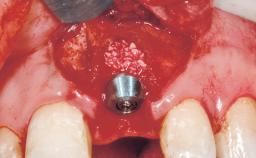

A 30-year-old female patient had lost tooth 21 and was referred to our clinic for consultation and treatment. Due to advanced apical infection, tooth 21 had been extracted two months earlier at another clinic and an acrylic-resin tooth had been bonded to the adjacent teeth. The patient desired implant treatment to avoid any damage to the adjacent natural teeth. While the patient had no history of any systemic disorder, she was a heavy smoker and exhibited medium to advanced periodontitis in the entire jaw. After the initial treatment to achieve a pocket probing depth of less than 4 mm and no bleeding on probing, a decrease in the height of the papillae mesial and distal to the extraction site and overall gingival recession were observed.

Bone Augmentation | Horizontal|Staged |

Augmentation Materials | Autogenous chips|Membrane |

Bone Volume | Deficient horizontally, requiring prior grafting |